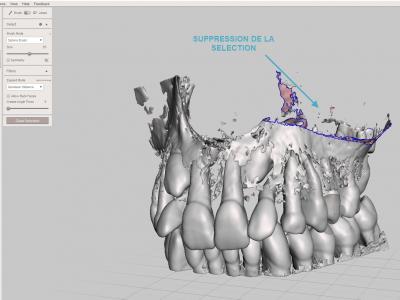

- Etape de nettoyage : il s'agit d'enlever tous les fragments osseux ou les zones non désirées. C'est l'étape la plus longue ! (Il faut penser à sauvegarder régulièrement pour éviter des accidents).

Sélectionner la surface de zone à éliminer avec l'outil "Select" "Brush", puis les supprimer avec le raccourci clavier "X"